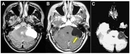

Tanı YöntemleriKafa içindeki lezyonların tanısı, genellikle hem klinik muayene hem de görüntüleme yöntemleri ile konulur. Kullanılan başlıca yöntemler şunlardır: